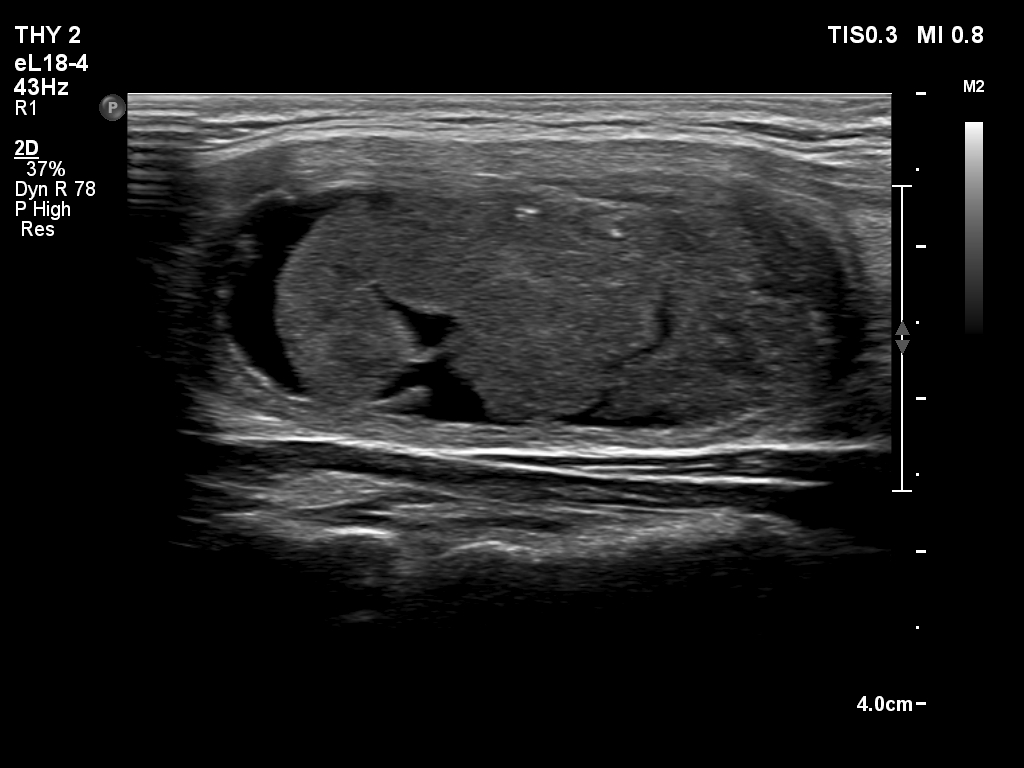

Second session of sclerotherapy (ultrasonographic picture 2)

Left lobe, longitudinal scan.